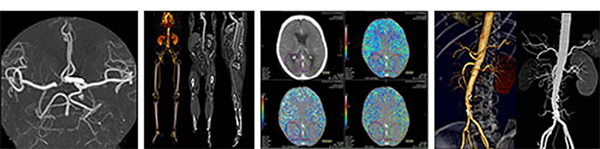

Vascular Imaging

Blood vessel imaging was previously performed with an interventional angiogram, but today CT scanning is taking angiography into a new frontier. Vessels are accurately evaluated with 3D scans performed non-invasively on an outpatient basis in just 10 minutes.